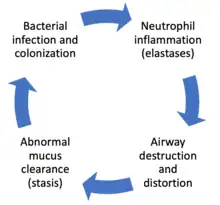

The development of bronchiectasis requires two factors: an initial injury to the lung (such as from infection, auto-immune destruction of lung tissue, or other destruction of lung tissue (as seen in gastroesophageal reflux disease or aspiration syndromes)) which leads to impaired mucociliary clearance, obstruction, or a defect in host defense.[21][3] This triggers a host immune response from neutrophils (elastases), reactive oxygen species, and inflammatory cytokines that results in progressive destruction of normal lung architecture. In particular, the elastic fibers of bronchi are affected.[13] The result is permanent abnormal dilation and destruction of the major bronchi and bronchiole walls.[62]

Disordered neutrophil function is believed to play a role in the pathogenesis of bronchiectasis. Neutrophil extracellular traps (NETs), which are extracellular fibers secreted by neutrophils that are used to trap and destroy pathogens, are hyperactive in bronchiectasis. Increased NET activity is associated with more severe bronchiectasis.[21] Neutrophil elastase, which is an extracellular protein secreted by neutrophils to destroy pathogens as well as host tissue, is also hyperactive in many cases of bronchiectasis.[21] An increased neutrophil elastase activity is also associated with worse outcomes and more severe disease in bronchiectasis.[21] The initial lung injury in bronchiectasis leads to an impaired mucociliary clearance of the lung airways, which leads to mucous stasis.[21] This mucous stasis leads to bacterial colonization in bronchiectasis which leads to neutrophil activation.[21] This neutrophil activation leads to further tissue destruction and airway distortion by neutrophils in addition to direct tissue destruction by the pathogenic bacteria.[21] The distorted, damaged lung airways thus have impaired mucociliary clearance; leading to mucous stasis and bacterial colonization leading to further neutrophil activation and thus fueling a self-perpetuating "vicious cycle" of inflammation in bronchiectasis.[21] This "vicious cycle" theory is the generally accepted explanation for the pathogenesis of bronchiectasis.[40]